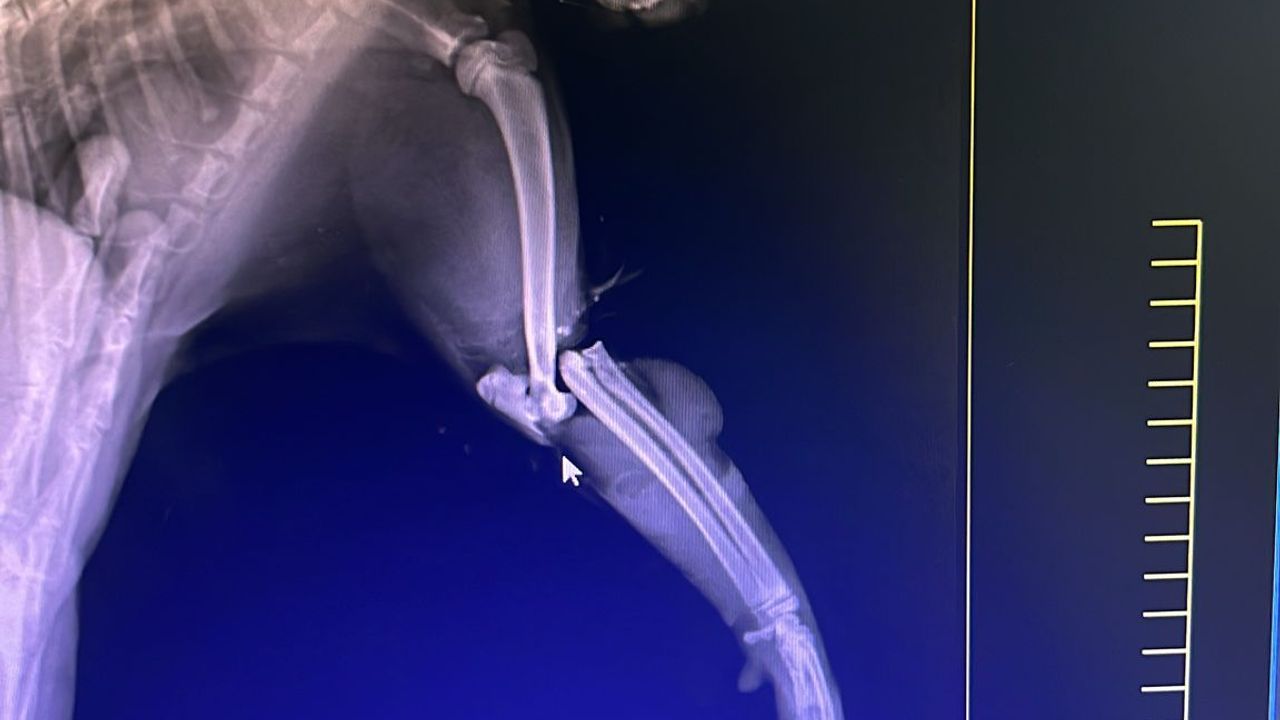

Veteriner hekimler tarafından yapılan ilk müdahalede, kedinin bacağında, omurgasında ve patilerinde kırıklar tespit edildi.

Ayrıca, kedinin kuyruğu da kaza sonucu kopmuş durumda. Omurgadaki iki kırık nedeniyle kedinin tedavisi için İstanbul’da bir veteriner kliniğine götürülmesi gerektiği belirtildi.